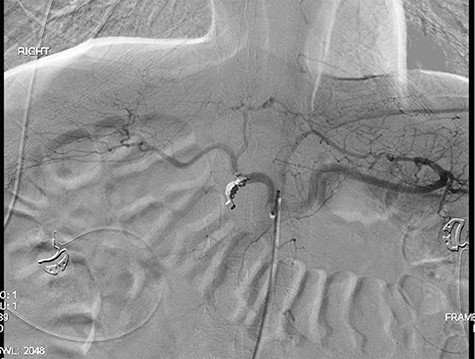

A 56-year-old African American male presented in 2015 with abdominal pain, with associated melena and hematochezia. The patient has a history of chronic back pain for which he takes 600 mg ibuprofen daily, alcohol abuse, tobacco use and a previous GI bleed in 2011, which necessitated 6 units (U) of packed red blood cells (PRBCs) and emergency therapeutic endoscopy. The patient was found to be hypotensive to 76/56 mm Hg, and hemoglobin (Hgb) was found to be 9.4 g/dl, from a previous baseline of 10.6 g/dl. His rectal examination was guaiac positive. A repeat Hgb was found to be 6.5 g/dl. The patient was given 3 U of PRBC and an emergency endoscopy was performed. On endoscopy, the patient was found to have a 6 cm gastric ulcer with an associated vessel underneath of a large clot. Due to the high risk nature of the bleed, it was felt by the gastroenterologist that the patient should undergo an endovascular angioembolization (Fig. 1). The patient was brought to the Interventional Radiology Suite for the procedure. The patient’s right common femoral artery was accessed and the celiac trunk was selected. A subselective common hepatic arteriogram was performed, which demonstrated active extravasation arising from the proximal aspect of the GDA. The GDA was then coil embolized both proximal and distal to the site of bleeding using five microcoils. Repeat arteriogram demonstrated no further opacification of the GDA and no further extravasation (Fig. 2).

Demonstrating active extravasation of the GDA during a subselective GDA arteriogram